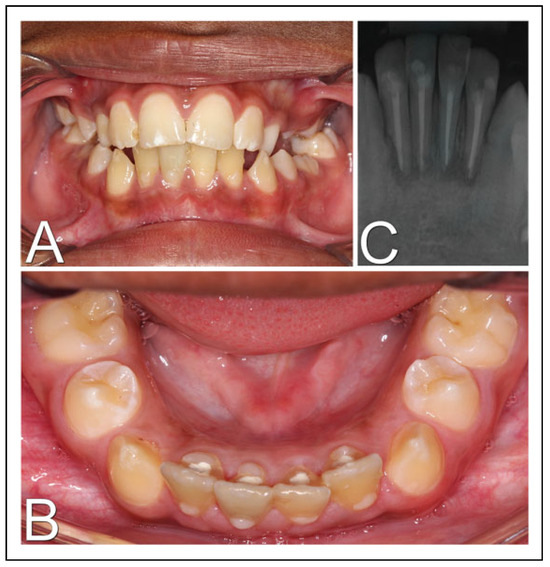

In second intervention, the use of titanium mini screws was not feasible due to the thin alveolar bone wall, as the stabilization of the screws could not be achieved, in addition to the risk of damage to dental germs. So, another treatment modality was chosen. Up with a new dental splinting, proceeded with a circummandibular cerclage using steel wire number 1, encompassing the base of mandible and the alveolar segment, bilaterally, between teeth 31 and 32 and between 41 and 42 (Figure 2A and B). In the immediate postoperative radiographic examination, a satisfactory fracture reduction and cerclage positioning were observed (Figure 2C and D). With this technique, greater stability of the dentoalveolar fragment and occlusion was achieved, allowing the local healing process. The patient received postoperative recommendations, mainly to maintain a soft diet.

Figure 2. Surgical procedure. (A) Transoperative photograph showing dentoalveolar segment stabilization by a circummandibular wire associated with a new dental splint; (B) intraoral photography in immediate postoperative period; (C) postoperative skull radiography in lateral position; (D) postoperative skull radiograph in posteroanterior position.